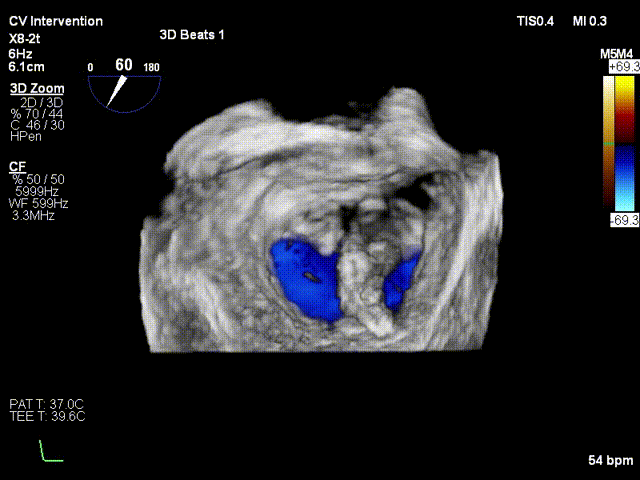

患者平卧导管床,常规消毒铺巾,呼吸机辅助呼吸,穿刺右侧股静脉,于经食道超声指导下穿刺房间隔,造影确认穿刺针位于左房后。予super stiff置入左上肺静脉。于右股静脉沿super stiff推送MitraClip Guide Catheter于左房。于经食道超声指引下,推送XTR Clip Delivery System至二尖瓣左房面,食道超声确认12点钟方向推送至二尖瓣左室面,重新调整DC handle使Clip Arm至11点钟方向。顺利捕捉二尖瓣前叶A3及后叶P3区域,Grap down后夹闭Clip Arm。经食道超声评估二尖瓣返流由MR4+减少至微量,确认前叶有效夹持长度13mm,后叶有效夹持长度为11mm,确认瓣叶夹持牢固,释放瓣膜夹。经食道超声再次评估二尖瓣返流微量,二尖瓣压差1mmHg,退出MirtaClip系统,3DTEE评估房间隔 穿刺口少量左向右分流,未见右向左分流,未见心包积液,结束手术。

患者平卧导管床,常规消毒铺巾,呼吸机辅助呼吸,穿刺右侧股静脉,于经食道超声指导下穿刺房间隔,确认穿刺针位于左房后交换房间隔穿刺导管至左房, 再予super stiff置入左上肺静脉;退出房间隔导管后予16F预扩张鞘扩张右股静脉;于右股静脉沿Super stiff推送24F MitraClip steerable Guide Catheter于左房, 于3DTEE指导下,推送NTR Clip Delivery System至二尖瓣左房面,3DTEE确认12点钟 方向推送至二尖瓣左室面,重新调整DC handle使Clip Arm至11点钟方向。顺利捕捉 二尖瓣前叶A1及后叶P1区域,Gripper down后夹闭Clip Arm,3DTEE评估二尖瓣反流 由MR4+减少至1+,确认A1有效夹持长度8mm,P1有效夹持长度8mm,确认瓣叶夹持牢固, 释放瓣膜夹,3DTEE再次评估二尖瓣反流1+;退出MitraClip系统,3DTEE评估房间隔 穿刺口少量左向右分流,3DTEE评估房间隔 穿刺口少量左向右分流,未见右向左分流,未见心包积液,结束手术。